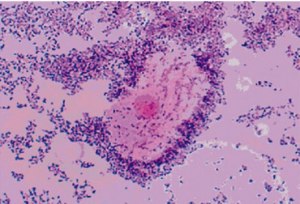

Ключевые клетки в гинекологическом мазке - это клетки эпителия, которые обладают характерным внешним видом и часто свидетельствуют о наличии бактериального воспаления, такого как бактериальный вагиноз. Эти клетки обычно образуются при увеличенном количестве бактерий во влагалище, что может привести к различным симптомам, таким как зуд, раздражение или необычный запах.

Норма ключевых клеток в гинекологическом мазке обычно составляет менее 20% от общего числа клеток. Превышение этого значения может указывать на наличие воспалительного процесса, который требует дополнительного обследования и лечения.